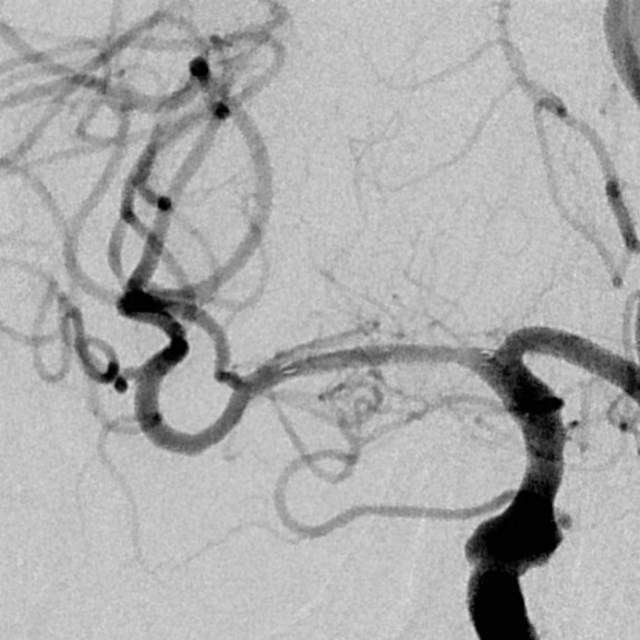

3、第三个患者:我们给予一期外科干预后,一个月后TTP检查发现,狭窄的部位和术后即刻相比是变差的,但与第一次术前相比好转。继续药物治疗狭窄部位存在进行性闭塞的风险。于是二期安全的植入支架,血流完全恢复正常,顺利出院。

一期干预后,一个月复查所见狭窄区为长节段、多发部位狭窄,与术后即刻相比变差了

继续药物治疗存在狭窄部位闭塞的风险,果断给予支架植入